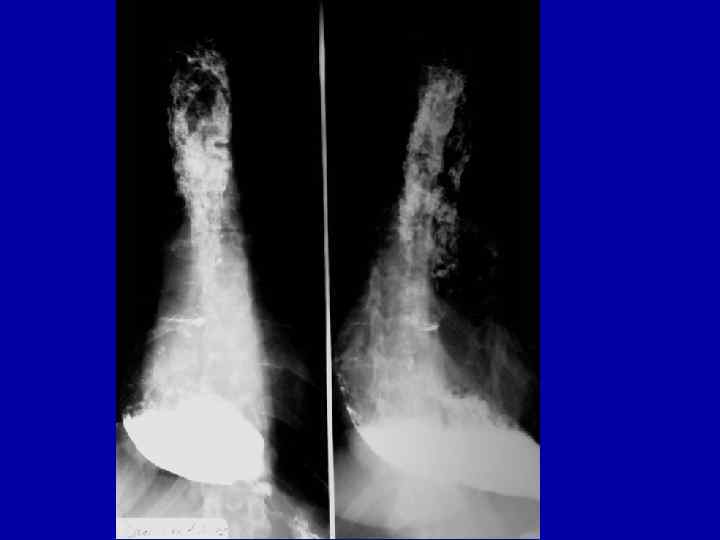

Кардиоспазм 2 степни

Кардиоспазм 2 степни

Кардиоспазм 3 степени